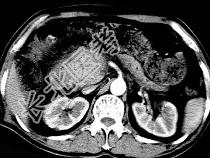

- 单项选择题男,50岁, 黄疸进行性加重、腹部胀痛不适、食欲减退、体重减轻、上腹部可触及肿块,CT如图, 最可能的诊断是 ( )

A、胰头癌

B、转移瘤

C、慢性胰腺炎

D、急性胰腺炎

E、腹膜后淋巴瘤